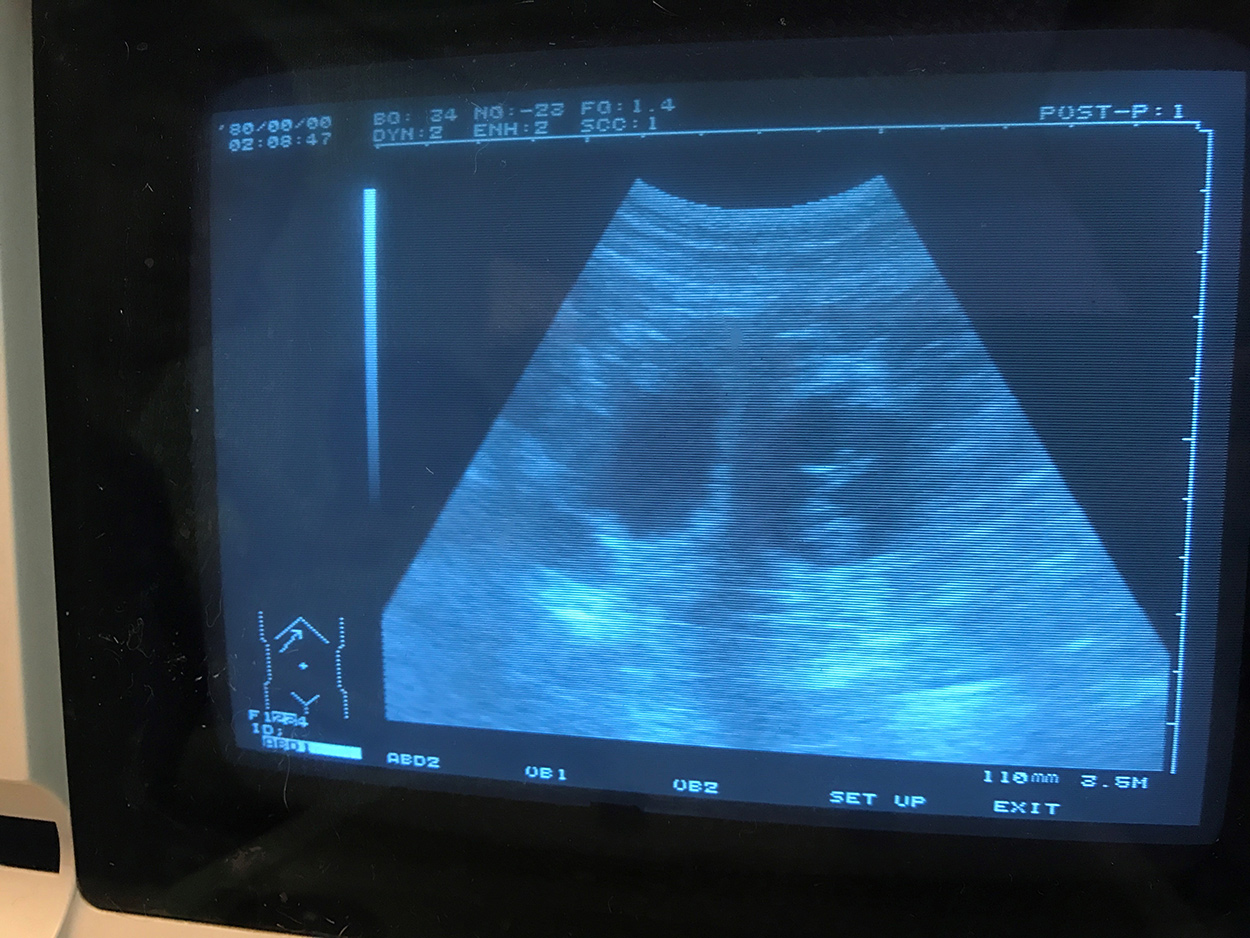

Zwangerschap bevestigd

Zwangerschap Kataum Inua's Tipsinartok bevestigd! Puppys'verwacht rond einde april.